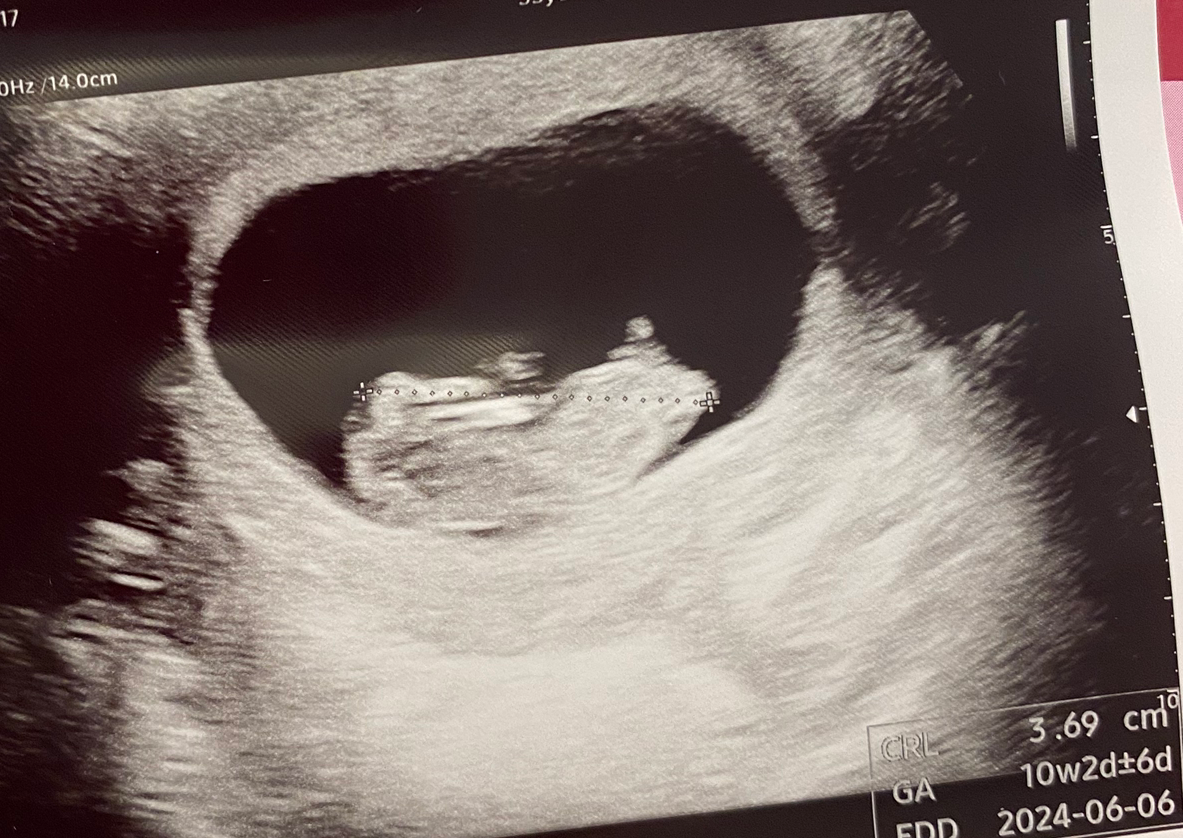

오랜만에 초음파를 보러 간 날. 10주 차이다. 이제는 누워서 배초음파로 편하게 볼 수 있었다!

초음파 기계를 대자마자 어느새 커져버려 마치 햄스터처럼 생긴 아기가 보였다. 손도 위아래로 움직이더니 다리까지 힘차게 움직이며 발차기를 하는 모습도 보였다! 나는 아무것도 느낄 수 없었지만 내 몸속에서 이렇게 열심히 움직이고 있다니 보고도 믿기지 않았다. 초음파 화질이 좋아서 정말 작은 손가락 발가락 모양도 볼 수 있었고 심장이 잘 뛰고 있는 것도 확인할 수 있었다. 이렇게 처음으로 움직이는 아기를 마주하게 되었다!

어플을 통해서 저장된 동영상을 다운로드하여 몇 번을 보았다. 손을 움직이고 발을 차는 모습, 그리고 발가락 모양이 잡힌 것을 몇 번이나 돌려보았다. 몸은 힘들지만 마음은 가벼웠다.